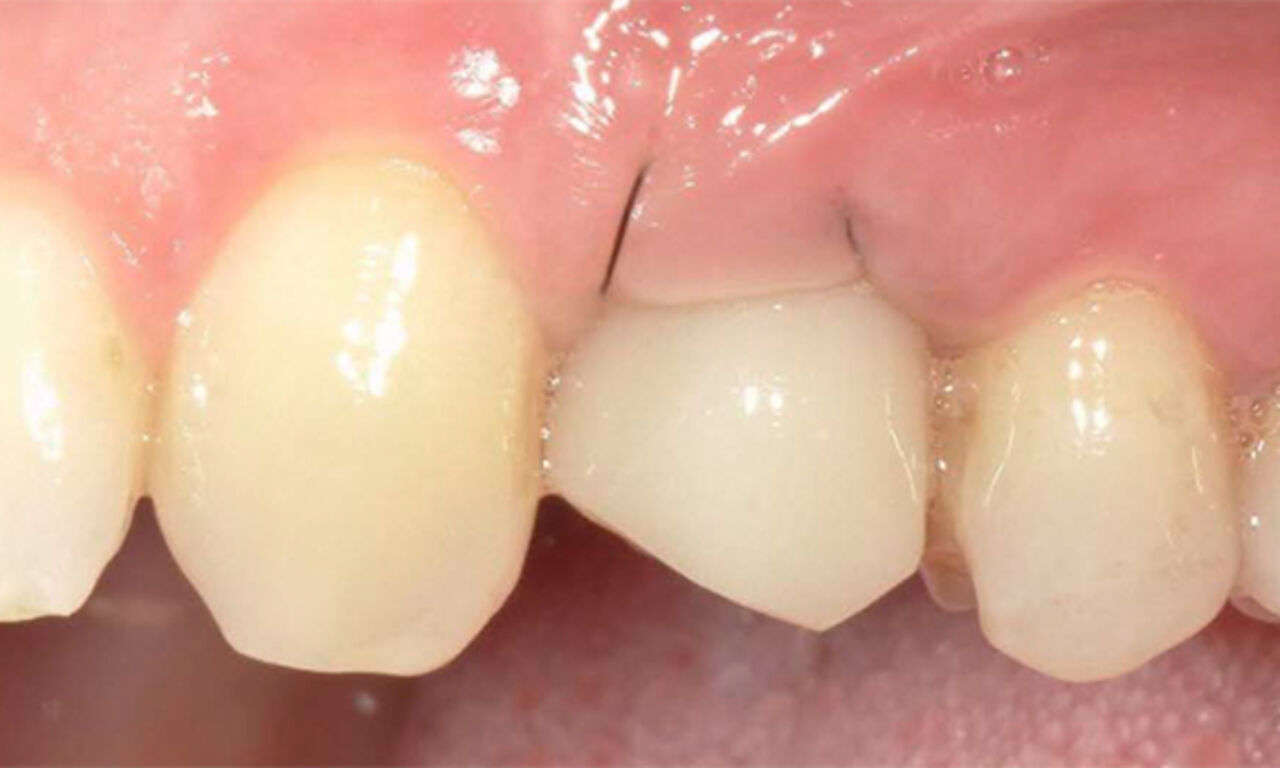

Exzellente Ästhetik

Langfristiger marginaler Knochenerhalt für eine exzellente Ästhetik über Jahre hinweg. Sie wissen, dass Sie gewonnen haben, wenn Ihr anspruchsvollster Patient dauerhaft zufrieden ist.

Die Hauptmerkmale des Implantats – EV-Innenverbindung, OsseoSpeed, MicroThread, Soft Tissue Chamber – wurden für das Astra Tech Implant System hinsichtlich Knochenerhalt und Ästhetik dokumentiert und klinisch erprobt.

SoftTissue Chamber – größeres Weichgewebevolumen und hohe Ästhetik